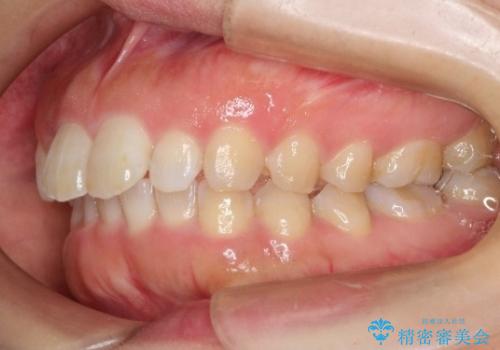

初診時の歯並びの状態としては、上の前歯が下に対して前に飛び出た上顎前突という状態で、前歯は大きく前に飛び出した状態により患者様も口の閉じづらさを感じているとのことでした。また上顎に軽度の叢生(ガタガタ)がありました。

抜歯は行わず上顎の奥のスペースを利用して歯をスライドする方法の他に歯列弓の拡大やディスキング(歯と歯の間の隙間を作る処置)を行い叢生を改善しました。